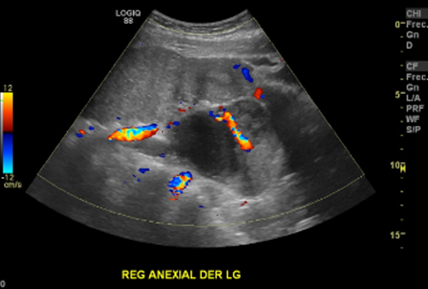

En región anexial derecha se observan 2 masas solidoquisticas, principalmente quísticas, bien delimitadas, tabicadas, con señal al doppler, sugerente de cistoadenocarcinoma

Destaca en este estudio dos quistes complejos en región anexial derecha con componente sólido nodular excéntrico, con leve vascularización periférica de 4,5 x 4,1 cm y 8,6 x 7,8 cm asociado a masa parauterina derecha en íntimo contacto con estos quistes, ecogénica, heterogénea, de contornos irregulares, con leve vascularización periférica, de aproximadamente 10,8x9,5 cm.

Quistes complejos en región anexial derecha (2) asociado a masa parauterina derecha y ascitis, hallazgos que podrían estar en relación a neoplasia ovárica. Es indispensable complementar estudio con TAC de abdomen y pelvis para mejor caracterización